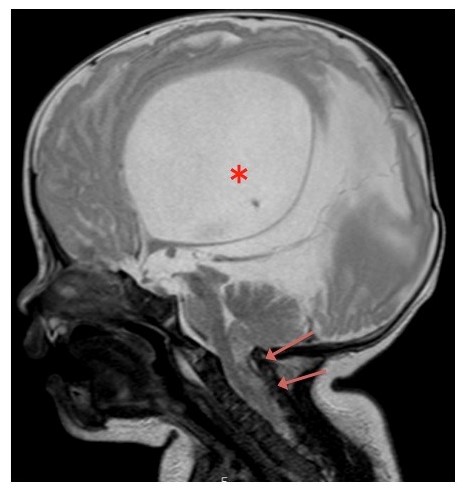

図2 キアリII型奇形のMRI画像 矢印は下垂した小脳扁桃と虫部を、*印は合併する水頭症を示しています。